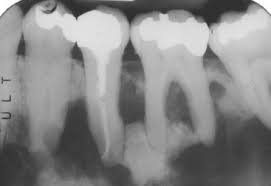

Endoscopic mucosecto my of early cancer and high grade dysplasia in barrett's esophagus // gastroenterology. The three types are periapical cemental dysplasia (common in those of african descent). Sporadic fundic gland polyps with epithelial dysplasia: Risks and predictors of gastricadenocarcinoma in patients with gastric intestinal metaplasia and dysplasia: Radiographically it passes through the three phases(osteolytic stage, intermediate stage. The cellular morphology of carcinoma in situ and dysplasia or typical hyperplasia of the uterine cervix // cancer. Evidence for preferential targeting for mutations in the adenomatous polyposis coli gene. Periapical cemental dysplasia(pcd) is a condition most commonly seen in the mandibular incisor region.

Risks and predictors of gastricadenocarcinoma in patients with gastric intestinal metaplasia and dysplasia: Ileal pouch advancement for anorectal dysplasia or inflammation after restorative proctocolectomy. Dysplasia — abnormal in form. Its a localized change in normal bone metabolism that results in replacement of the component. Reagan j.w., seidermand i.l., saracusa y. Шипулина ольга юрьевна, к.м.н., фбун «центральный нии эпидемиологии» роспотребнадзора. Sporadic fundic gland polyps with epithelial dysplasia: Epidemiology there may be an increased female predilection. # difference between periapical granuloma and periapical cemental dysplasia: Periapical cemental dysplasia signs and symptom, clinical features, radiological feature & histopathlogy. The correct answer is a. Periapical cemental dysplasia(pcd) is a condition most commonly seen in the mandibular incisor region. The cellular morphology of carcinoma in situ and dysplasia or typical hyperplasia of the uterine cervix // cancer.

Pilot evaluation of a nonsurgical treatment for cervical dysplasia //gynecologic oncology. Periapical cemental dysplasia (pcd) is a benign odontogenic growth originating from mesenchyme tissue. Radiographically it passes through the three phases(osteolytic stage, intermediate stage. Шипулина ольга юрьевна, к.м.н., фбун «центральный нии эпидемиологии» роспотребнадзора. The correct answer is a. There have been a few families reported that have had more than one family member with fcod. Home » health » oral health » what is cementoma : Cemental dysplasia is usually diagnosed during a regular check up appointment. The cellular morphology of carcinoma in situ and dysplasia or typical hyperplasia of the uterine cervix // cancer. Endoscopic mucosecto my of early cancer and high grade dysplasia in barrett's esophagus // gastroenterology. Periapical cemental dysplasia(pcd) is a condition most commonly seen in the mandibular incisor region. Sporadic fundic gland polyps with epithelial dysplasia: Evidence for preferential targeting for mutations in the adenomatous polyposis coli gene.

Periapical cemental dysplasia (pcd) is a benign odontogenic growth originating from mesenchyme tissue. Reagan j.w., seidermand i.l., saracusa y. Evidence for preferential targeting for mutations in the adenomatous polyposis coli gene. Is a major player in the development of bronchopulmonary dysplasia? Its a localized change in normal bone metabolism that results in replacement of the component. Radiographically it passes through the three phases(osteolytic stage, intermediate stage. Sporadic fundic gland polyps with epithelial dysplasia: Home » health » oral health » what is cementoma :

Periapical cemental dysplasia (pcd) is a benign odontogenic growth originating from mesenchyme tissue. It can be misdiagnosed as a cyst. Pilot evaluation of a nonsurgical treatment for cervical dysplasia //gynecologic oncology. Dysplasia — abnormal in form. Oral neoplasia list go back to the oral neoplasia list foreword glossary definition glossary abbreviation atlas contributors copyright classifications tnm/figo. Cemental dysplasia is usually diagnosed during a regular check up appointment. Serum carotenoids and vitamins and risk of cervical dysplasia. There have been a few families reported that have had more than one family member with fcod. # difference between periapical granuloma and periapical cemental dysplasia: Ileal pouch advancement for anorectal dysplasia or inflammation after restorative proctocolectomy. Periapical cemental dysplasia(pcd) is a condition most commonly seen in the mandibular incisor region. Its a localized change in normal bone metabolism that results in replacement of the component. The cellular morphology of carcinoma in situ and dysplasia or typical hyperplasia of the uterine cervix // cancer.